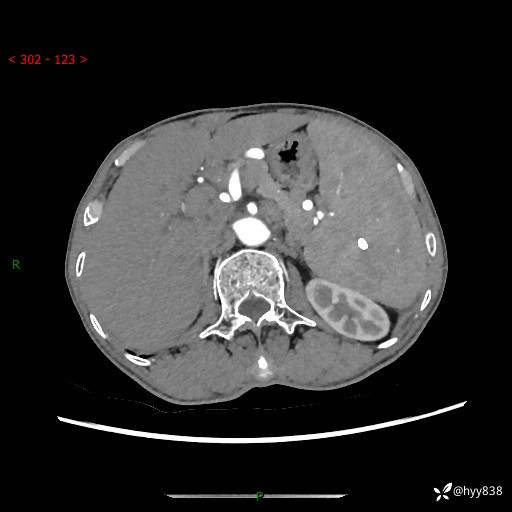

老年男性,脾大并脾脏弥漫粟粒状低密度,淋巴瘤 VS 肉芽肿 VS 血管瘤---结果公布

简要病史: 患者于3月前无明显诱因出现脾大,伴腹部轻微不适,具体不详,无腹痛、腹泻、腹胀,无头晕、头痛、乏力,无恶心、呕吐、呕血,无胸闷、气短、胸痛不适

上腹部CT平扫+增强